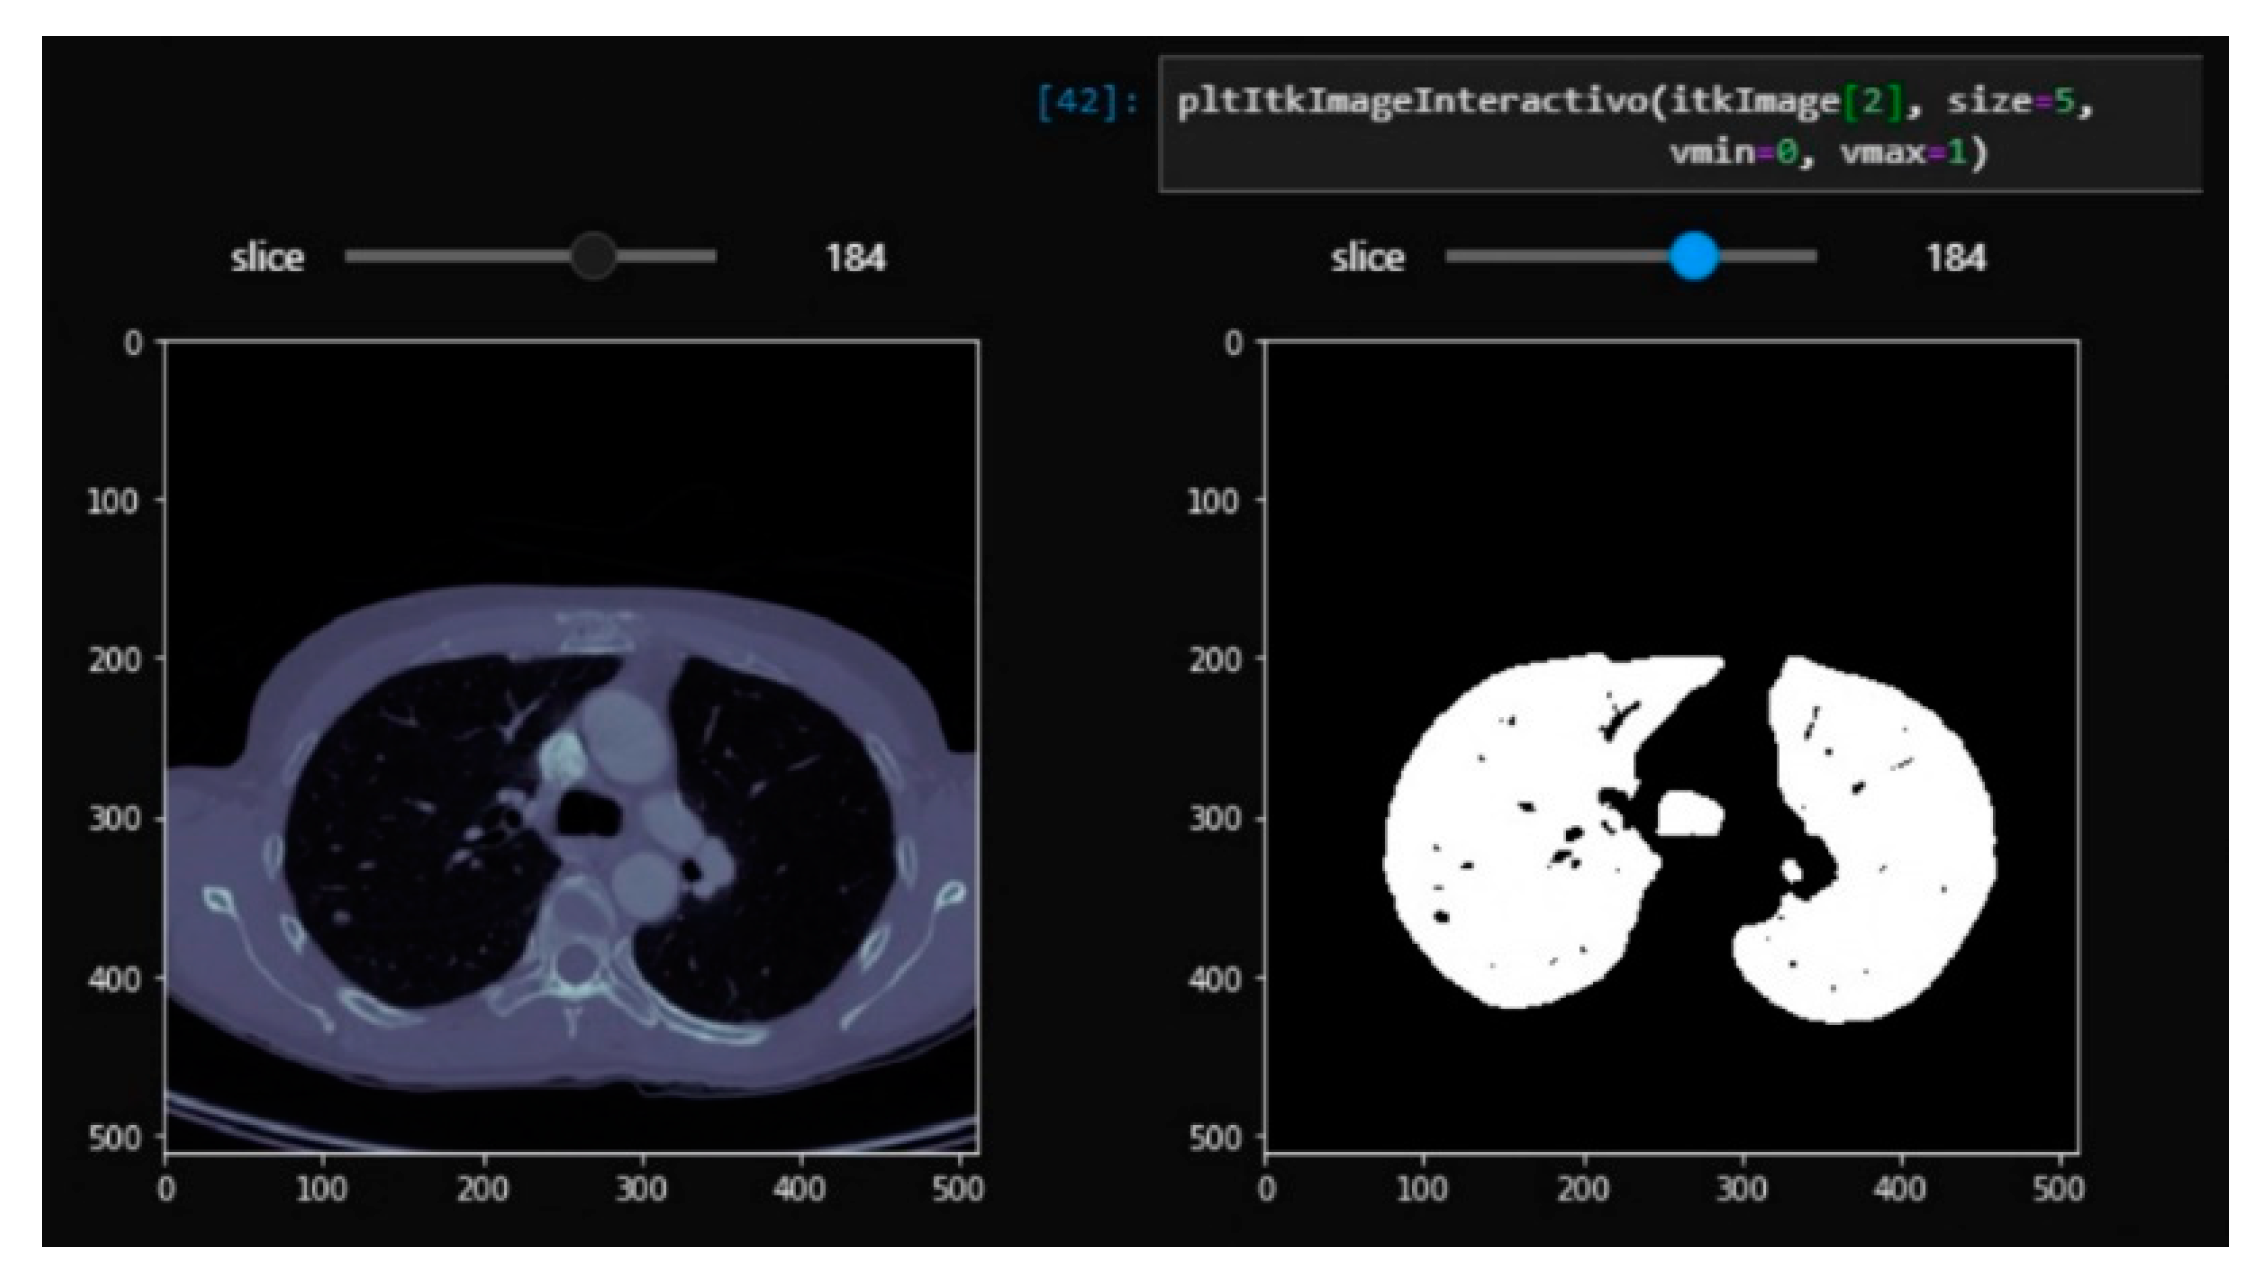

3.1. From dicom to 3D Models with Automatic Segmentation

3.2. Results Visualization